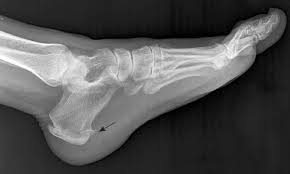

족저 근막염은 발바닥의 족저 근막에 반복적인 스트레스가 가해져 염증이 생기는 질환입니다. 이로 인해 발바닥, 특히 발뒤꿈치 부분에 통증이 발생하는데, 주로 아침에 일어났을 때 가장 심한 통증을 느끼게 됩니다. 족저 근막염은 비만, 운동 부족, 잘못된 신발 착용 등 다양한 원인으로 발생할 수 있는데, 이러한 원인을 파악하고 족저 근막염 치료법을 적용하는 것이 중요합니다. 통증이 심해지면 일상생활에 큰 지장을 초래할 수 있으므로 조기에 치료하는 것이 좋습니다.